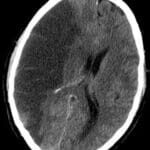

ICH